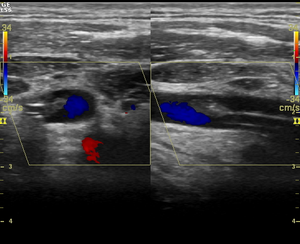

Дуплексное исследование сосудов

- Исследование в В-режиме конвексным датчиком и линейным датчиком

- Исследование в режиме ЦДК и ЭДК и спектрального доплера